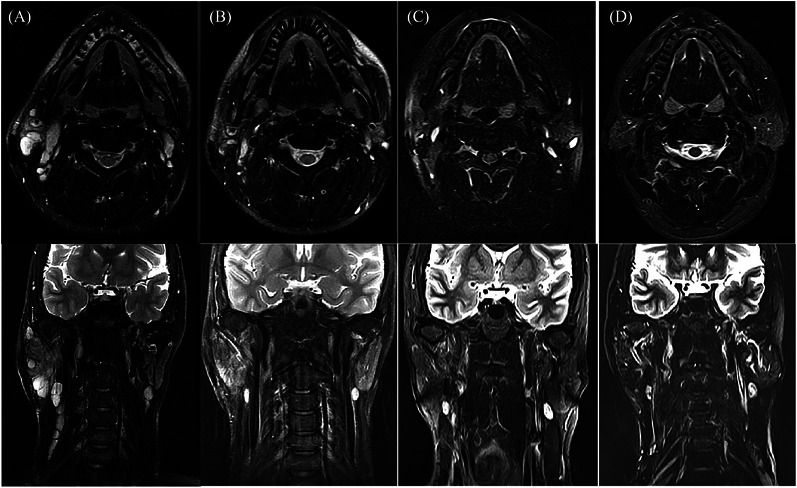

Abstract Image